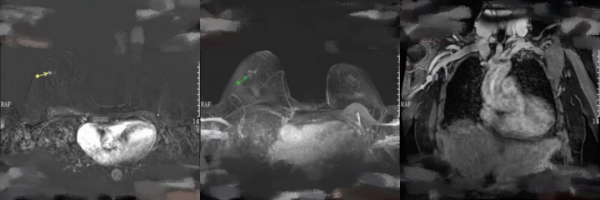

2021年11月21日,4個週期THP新輔助治療後乳腺MRI複查提示:與2個週期TCbHPy新輔助治療(圖4)相比,右乳外上象限見簇狀分佈強化結節,較大約0.5cm,T1WI呈低訊號,T2WI呈高訊號,未見明顯彌散受限,TIC曲線呈流出型;雙乳見一大小約0.3cm強化結節,邊界清,TIC曲線呈流入型;兩側腋窩未見明顯腫大淋巴結;雙側胸大肌未見明顯異常;雙側面板、皮下、乳頭及乳暈未見明顯異常訊號(圖5)。